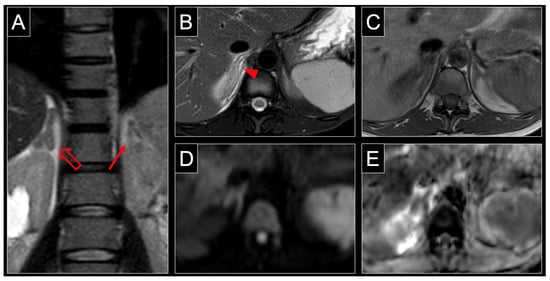

Figure 2.

MRI of a 31-year-old patient at 34 weeks of pregnancy with non-hemorrhagic infarction of the right adrenal gland. Note the characteristic enlargement of the right adrenal gland (hollow arrow) compared to the normal contralateral adrenal gland (solid arrow) in the coronal plane of a T2 weighted sequence (A). Axial T2 weighting with fat saturation shows central and surrounding hyperintensity (arrowheads) reflecting organ edema with inflammatory response of retroperitoneal fat (B). The lack of intraparenchymal hyperintensity (arrowhead) in T1 weighting (C) indicates the absence of acute hemorrhage. Similar to other body regions, organ infarction is associated with restricted diffusion, which manifests as hyperintensity at high b-values, such as 800 s/mm2 (D) and low values in the ADC map (E) of DWI. ADC = apparent diffusion coefficient, DWI = diffusion weighted imaging.